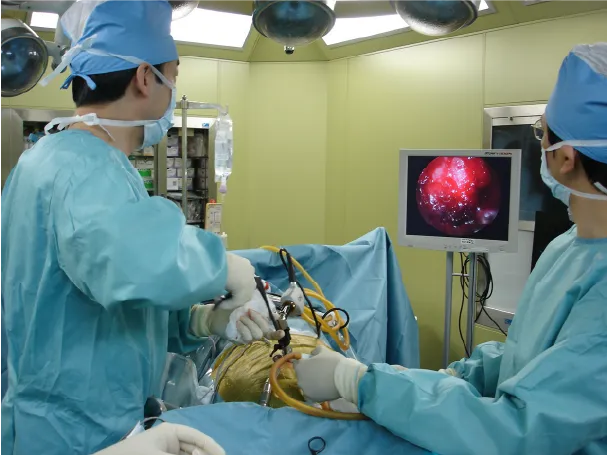

腰椎椎間板ヘルニアに対するMED法

-

モニターを見ながら行う手術風景 -

小さな傷で手術可能 -

MRI(左:術前 右:術後)